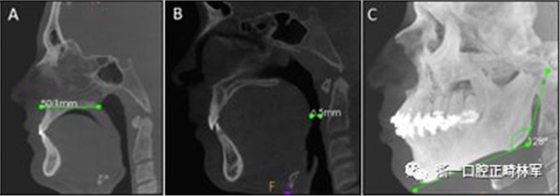

下頜骨前后角度的測量(下頜AP角),下頜橫角(TA下頜骨)和舌骨橫角(TA舌骨)。測量結(jié)果列于表I和圖1-4中。

圖1. A,ANS-PNS距離; B,最短距離; C,下頜AP角。